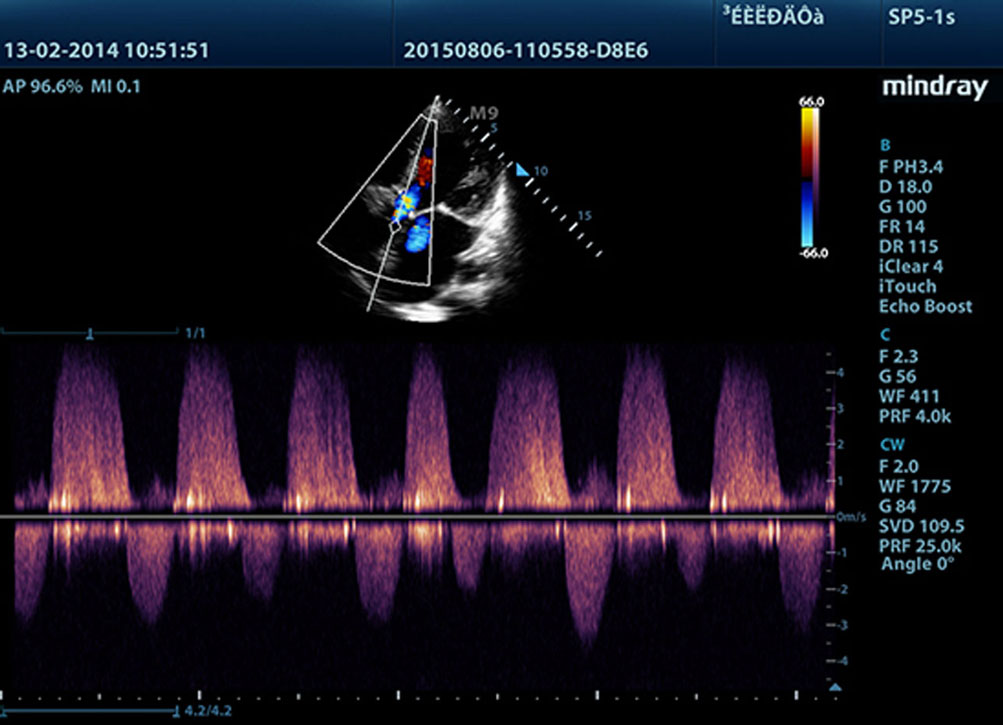

Daha belirgin g?rĂŒntĂŒler sa?layan, M9 ile uyumlu tĂŒm problar Mindray'in benzersiz 3T prob teknolojisiyle teslim edilir. Single crystal teknolojisinin eklenmesiyle gĂŒcĂŒ artan M9, ?zellikle zorlu hasta taramas? s?ras?nda daha iyi penetrasyon ve dinamik renk ak??? olana?? sunar.

?evredeki parazit gĂŒrĂŒltĂŒleri bast?r?rken gĂŒ?sĂŒz eko sinyallerini art?rmak i?in ba??ms?z sinyalden-gĂŒrĂŒltĂŒye bilgisini kullanmak ĂŒzere tasarlanm?? ak?ll? eko tespit ?zelli?i ile Mindray'in benzersiz uyarlanabilir sinyal i?leme teknolojisi, daha dengeli g?rĂŒntĂŒ parlakl??? ve miyokard doku katmanlar?n?n daha iyi g?rĂŒntĂŒlenmesini sa?lar.